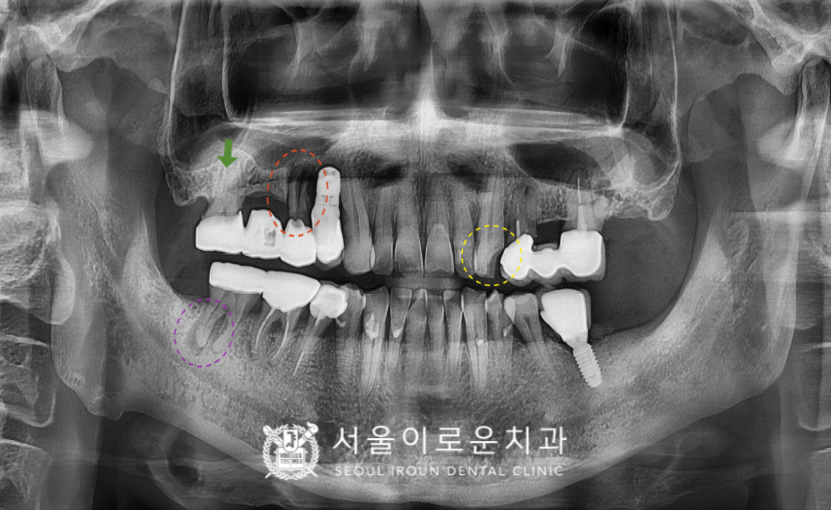

처음 내원 당시

환.자분의 파노라마 사진을 살펴보면

노란색 동그라미 표시의

위턱 왼쪽 송곳니(#23)이

충치로 인해 치아머리가 파절 되어 있어

신경치료 후 크라운 수복이 필요하였으며,

빨간색 동그라미 표시의

위턱 오른쪽 작은 어금니(#15)는

치아 뿌리가 파절되어 있어 발치 후

기존 상실된 첫 번째 큰 어금니(#16)와 함께

상악동 거상술을 동반하여

임플란트 식립이 필요하였습니다.

초록색 화살표의

위턱 오른쪽 두 번째 큰 어금니(#17)는

브릿지 제거 후 상태 평가 후

다시 크라운 수복 계획을

진행하기로 하였으며,

보라색 동그라미 표시의

아래턱 오른쪽 두 번째 큰 어금니(#47)는

타진 검사와 씹.는 검사에서

증.상이 있으며,

치아 뿌리 끝으로 병소가 관찰되어

신경치.료 후 크라운 치료가 필요했는데요.